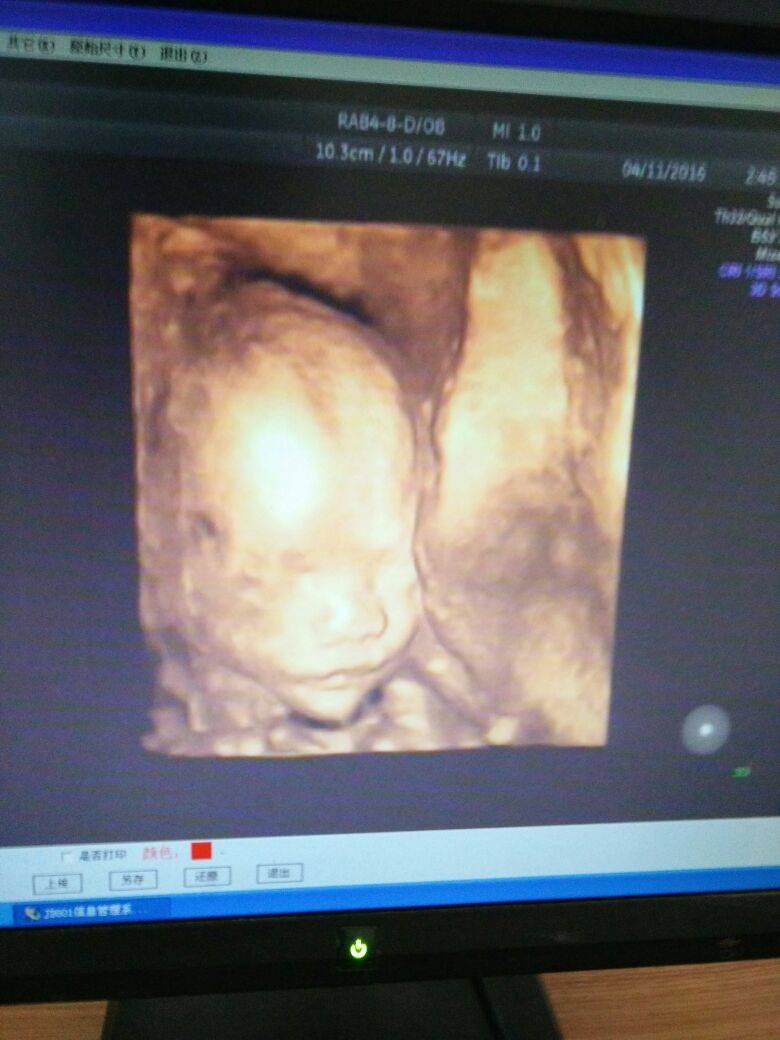

附上一个月前做四维的照片,这是妈妈第一次看见宝宝,大嘴巴长得好像爸爸啊!

你在想什么呢?表情如此享受?嘿嘿。